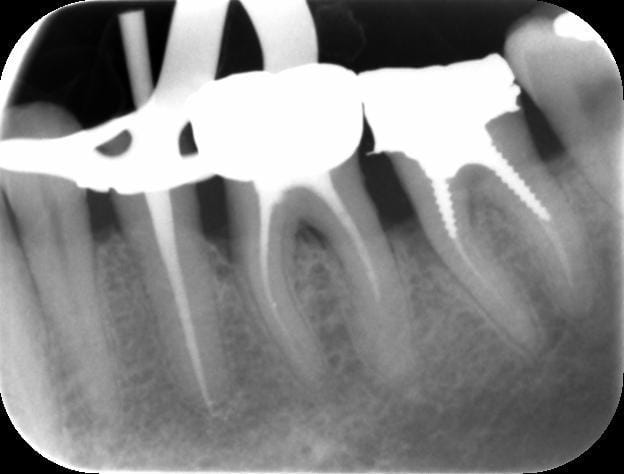

Fais nous la plutôt sur les molaires, qu'on rigole un peu plus